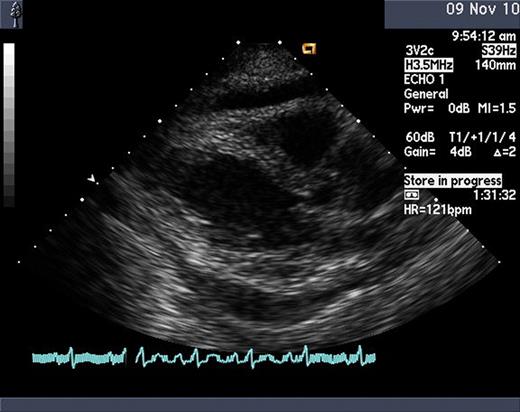

A 69 year old woman with a history of well controlled hypertension and a single episode of viral pericarditis initially presented to her physician with persistent leukocytosis and anemia. Bone marrow biopsy and aspiration revealed acute monocytic leukemia (FAB M5b) with normal cytogenetics. Induction chemotherapy was given with idarubicin 12 mg/m2 for 3 days and continous infusion cytarabine 200 mg/m2 for 7 days. Repeat bone marrow biopsy and aspiration on day 14 showed complete remission. Consolidation chemotherapy was administered with idarubicin 12 mg/m2 for 2 days and continuous infusion cytarabine 100 mg/m2 for 5 days. Prior to discharge from the hospital, she developed sudden onset of substernal chest pain associated with tachycardia and shortness of breath. Physical exam did not reveal jugular-venous distension; however, a slight friction rub was auscultated. Development of a pericardial effusion was suspected. Chest roenterogram demonstrated a mildly enlarged cardiac silhouette with a small left pleural effusion. Serum troponin-I and beta natriutretic peptide levels were within normal limits. Transthoracic echocardiogram was performed immediately which showed a moderate pericardial effusion with right ventricular collapse consistent with pericardial tamponade. A pericardial drain was placed which drained 900 cc of serous fluid. Laboratory studies on the fluid showed WBC of 6,500, LDH 1069, glucose 93, RBC 150, total protein of 4.1, albumin of 2.1 and pH of 7.0. Cultures did not yield bacterial or viral growth. Cytological analysis did not reveal evidence of leukemia. Based on these findings, a diagnosis of cytarabine induced pericardial effusion was strongly suspected.